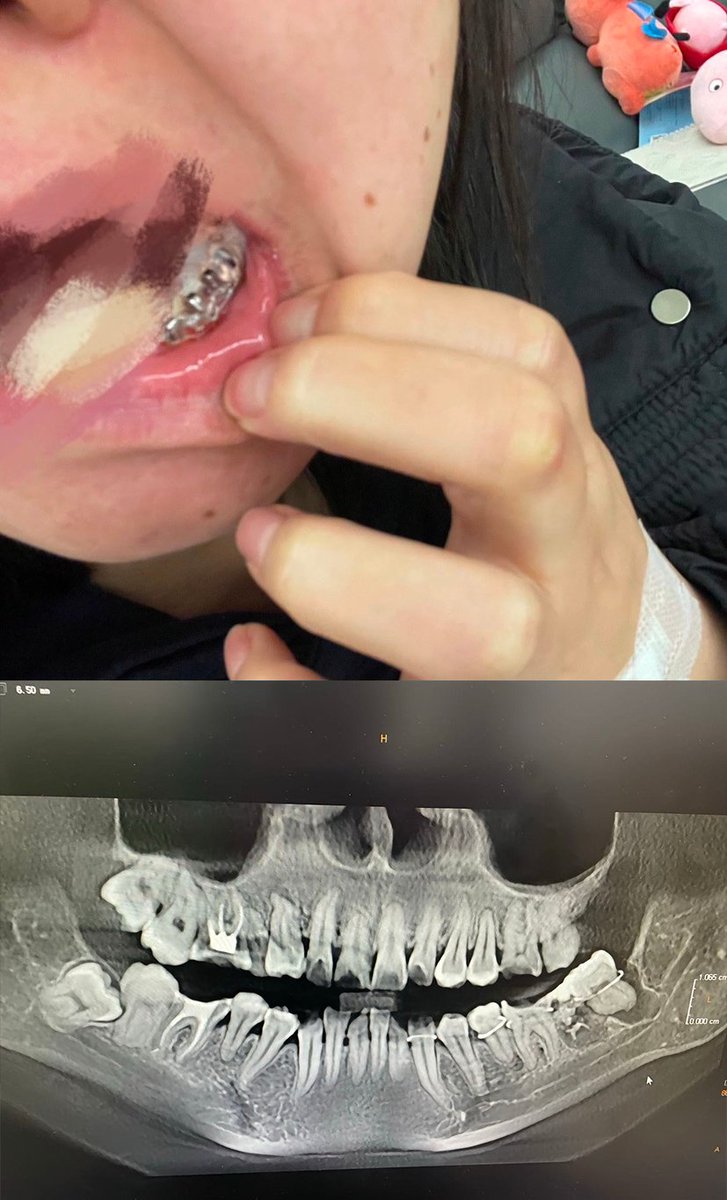

@yulinlunai28338 @whyyoutouzhele 是可以不拔 但是智齿因为长在最里面 很容易清理不到位然后最后也会坏成蛀牙 而且支持基本1年折腾你一回 智齿是毫无作用的牙齿 迟早都得拔

@whyyoutouzhele 我感覺拔智齒是多餘的。我覺得就是一部分想辦法坑人賺錢而已。古代人都不拔都活得挺好的。如果古人有那種智齒問題肯定會在詩詞裡講,但是都沒有,也就是說可以確定智齒是不用拔的。